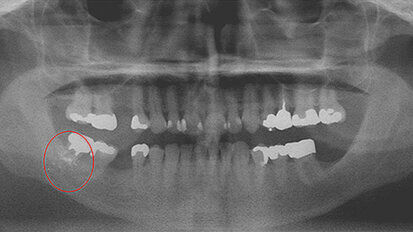

Foreign bodies discovered during routine dental treatment

While numerous medical reports and studies describe foreign bodies embedded in the soft tissue of the oral cavity either by traumatic injury or caused ...